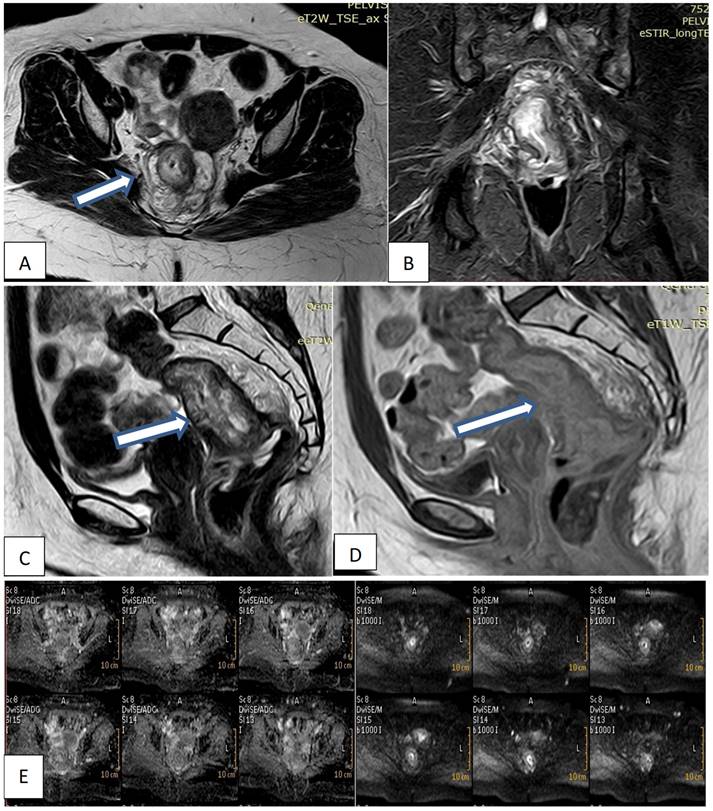

Pelvic MRI was performed on a 1.5 T magnet (Philips Acheiva, Guildford Business Park, Guildford, Surrey, Netherlands) with pelvic phased array coil and rectal gel administration. All patients underwent imaging while in the prone position following the placement of a small Foley catheter in the rectum and insufflation of approximately 200 to 300cm of room air. A sagittal fast-spoiled gradient echo sequence was used to localize the lesion. This was followed by axial, conventional, and spin echo T2-weighted images. Coronal and sagittal fast spin echo T2- weighted images were obtained. Post-contrast T1, Diffusion-weighted images. All images were interpreted by the same radiologist. Reporting was made regarding the depth of invasion of the rectal wall, adjacent organ involvement, and the presence of lymphadenopathy.

MRI interpretation criteria: A-T staging interpretations

• T1 was staged if the tumor was confined to the mucosal layer of the rectal wall.

• T2 was staged if there was an invasion of the rectal layer up to the muscularis propria with no penetration of the muscularis propria or perirectal fat.

• T3 was staged if there was an invasion of all rectal layers with perirectal fat infiltration yet without pelvic organ involvement.

• T4 was staged if there was an invasion of the mesorectal fascia and visceral peritoneum or surrounding organ infiltration.

B- Lymph node staging interpretations

• N0 was diagnosed if there was no lymph node metastasis.

• N1 was diagnosed if there was metastasis in one to three lymph nodes.

• N2 was diagnosed if there was metastasis in four or more perirectal lymph nodes (Fig. 1).

Figure 1

Female patient 47years old with mucinous rectal mass. (A, B, C) Axial & sagittal T2W & coronal STIR MRI images show transmural circumferential thickening about 7.5cm length & 6cm from the anal verge, invading muscularis propria & reaching perirectal fat, not infiltrating levator ani (T3c). (D) Sagittal T1W1 with contrast shows faint enhancement. (E) DWI & ADC images show restricted tumor tissue.